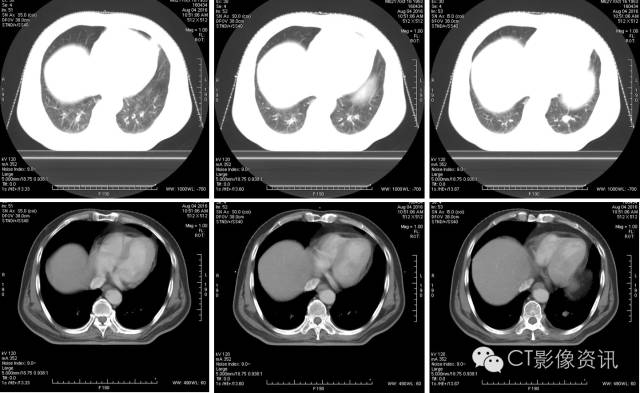

A4D软件测量

呼气末

吸气末

使用A4D软件测量,肿瘤随呼吸周期的运动幅度近24mm。

扫描结束之后,使用Advantage 4D软件可把图像分成10个呼吸期相,生成MIP图、AveIP图和minIP图。使用Advantage SIM MD软件可以在4D运动的图像上实时勾画和修改靶区,确定肿瘤ITV,比过去凭经验外扩范围的方式,可更精确的确定肿瘤放射治疗的范围。此外,在Advantage SIM MD上勾画的靶区文件为RT DICOM格式,可以发送给TPS(放疗计划系统),TPS不仅可以读取,如有需要还可进行编辑。